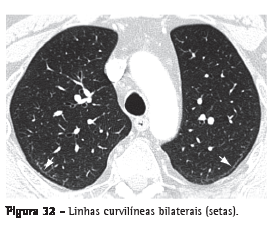

Linha curvilínea subpleural

Opacidade curvilínea de 1-3 mm de espessura, de localização subpleural, com distribuição paralela a sua superfície (Figura 32). É um indicador não específico de atelectasia, edema, fibrose ou inflamação.(3,7)